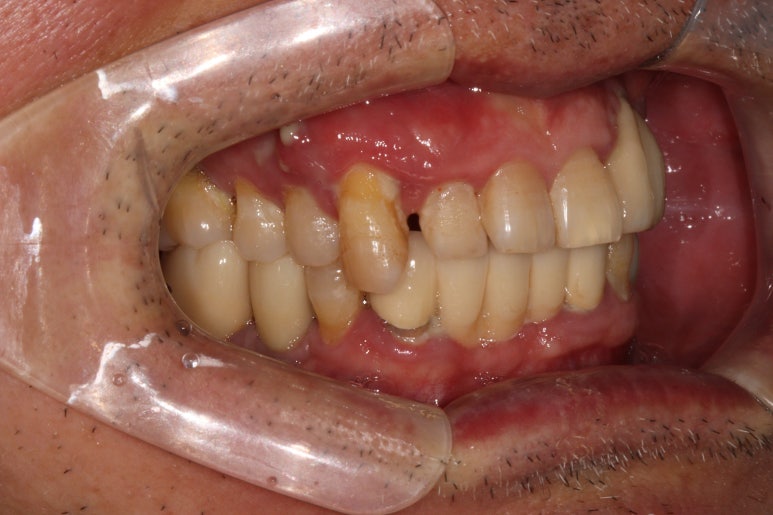

딱 봐도 만성 치주염이 너무 심해서 고름이 맺혀있는 것을 보실 수 있죠..

이미 병적 치아 이동 상태 (pathologic migration)이 심해서 치아는 내려오고 치아 사이 틈은 더 벌어진 상황.

속된말로 치아가 둥둥 떠있었습니다.

이런 경우 저는 단호하게 앞니 임플란트 말고 앞니 브릿지를 권해드립니다.

그 이유가 앞에 나왔죠? 잇몸뼈를 너무 많이 잃어버린 상황에서 임플란트를 억지로 하면 임플란트 크라운이 너무 길어져 보기에도 안좋고 음식도 많이 끼고 결과적으로 임플란트 주위염에 시달릴 것이 뻔하기 때문이죠.

보시면 치아의 병적 이동으로 이미 자기 자리에서 한참 이탈해버린 오른쪽 위 송곳니를 보실 수 있습니다.

참고로 송곳니까지 앞니라고 합니다!